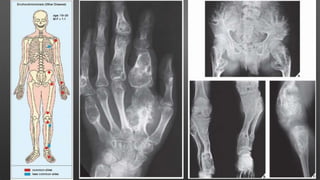

Enchondromatosis (Olliers Disease)

• Multiple enchondromas in metaphysis and diaphysis

• C/F: Knobby swelling of digits and gross disparity of

limb lengths

• Disease has strong preference for one side of body

• No hereditary or familial tendency

• Pathogeneses- Formation of ectopic nests and

failure of Chondrocytes and growth plate to mature

• Conventional radiography usually sufficient

Mafucci Syndrome

• Enchondromas with venous

malformations or spindle cell

hemangiomas

• Distribution of lesions similar to

Ollier Disease

• Unilateral in 50% cases

• Radiograph- Multiple

enchondromas associated with soft

tissue swellings and phleboliths